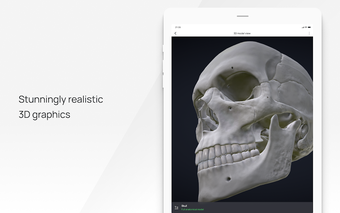

All 3D pathology models are developed in close cooperation with medical experts of hospitals and research centers. They are thought out to the very smallest detail. Each category contains models of healthy organs.

VOKA Pathology 3D is an educational tool for medical students, lecturers, and physicians. It can help you learn about human anatomy and pathology.